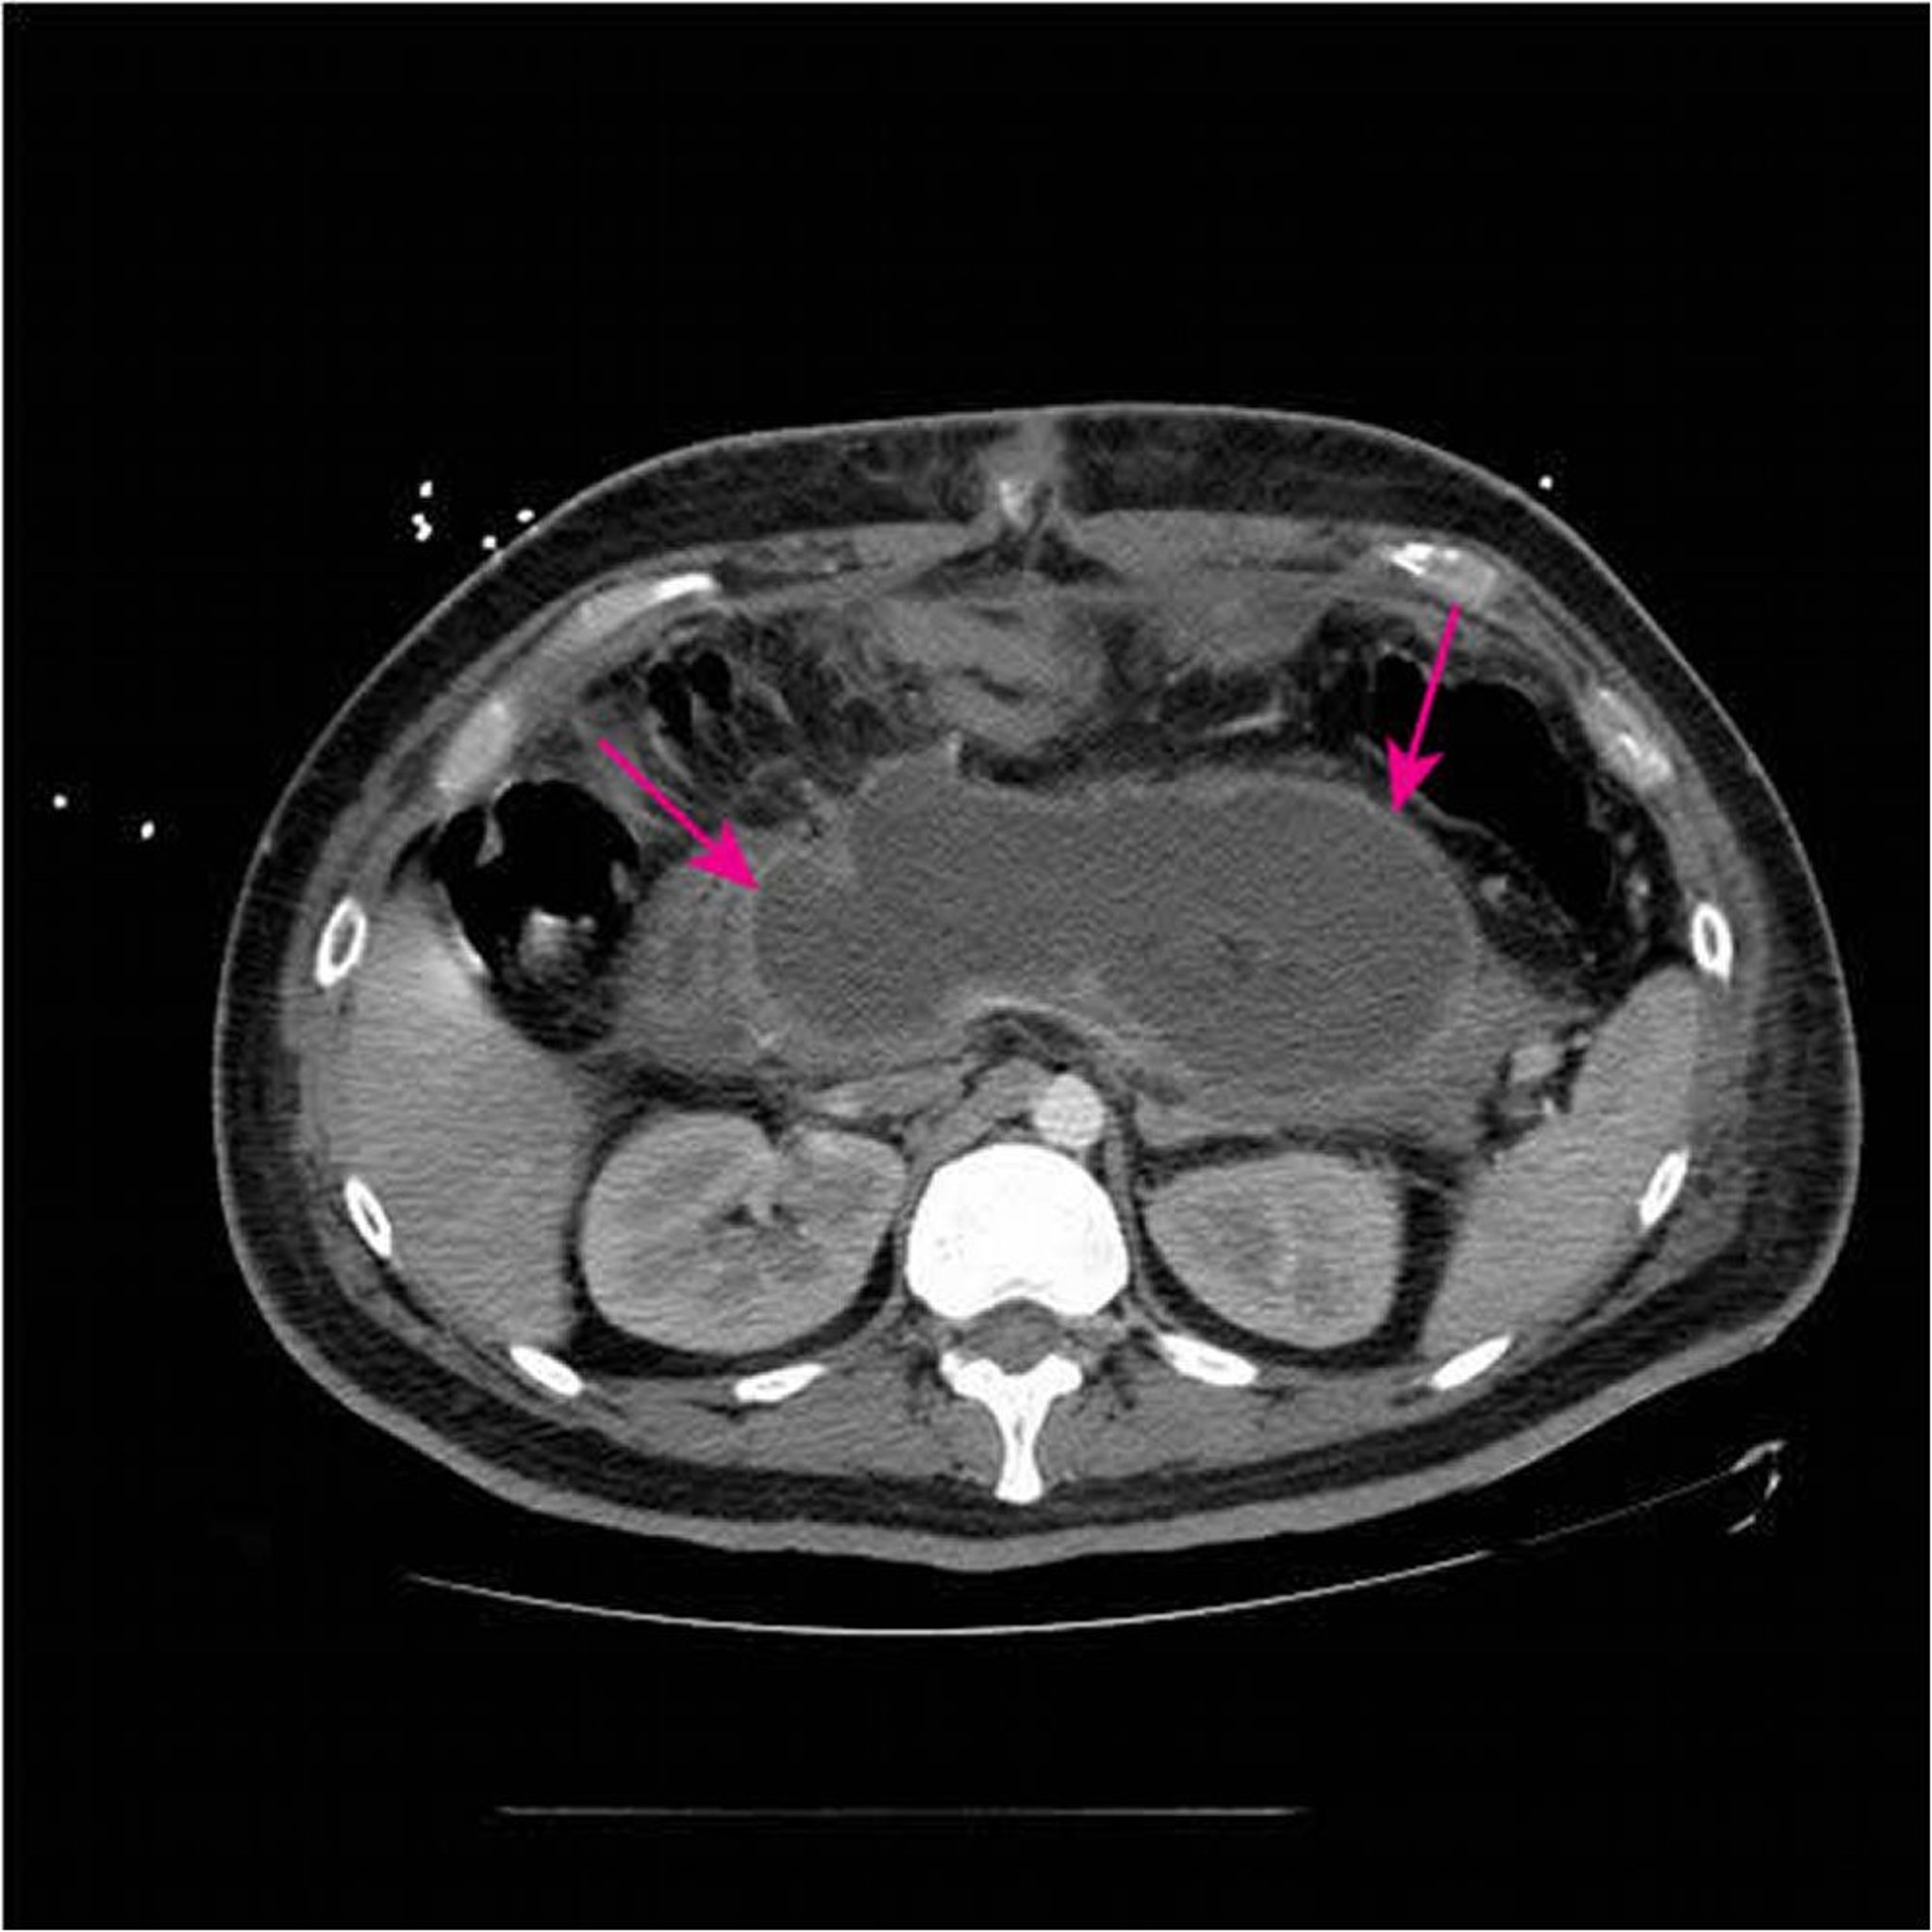

Akute nekrotisierende Masse

Dieser CT-Scan mit intravenösem und oralem Kontrastmittel zeigt eine große, akute nekrotisierende Masse (Pfeile), die den größten Teil des Pankreasgewebes ersetzt < 4 Wochen nach Erstvorstellung einer nekrotisierenden Pankreatitis.

Image courtesy of Sonam Rosberger, MD.